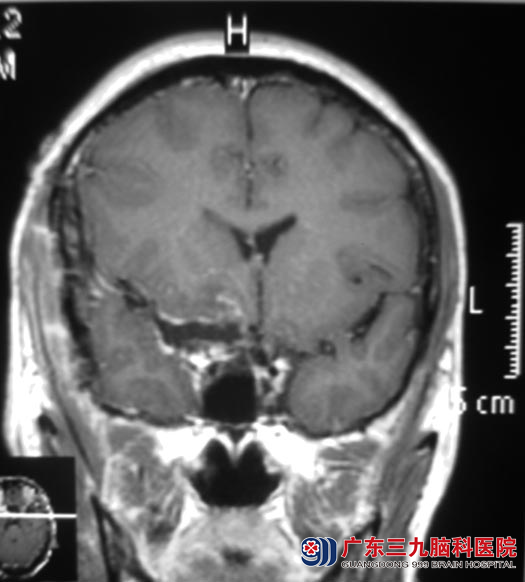

逐渐的,药物也没有效果,同时伴有额颞部间断性疼痛。当地医院行头颅CT检查提示:右侧鞍旁占位,考虑脑肿瘤。广东三九脑科医院头颅MR检查提示“右侧蝶骨嵴脑膜瘤,大小约3.1cm×3.1cm×3.5cm,考虑脑膜瘤”,CTA示“右侧颈内动脉及其分支与肿瘤关系密切”。

完善相关检查后,综合神经外科 鲁明主任主刀,在全麻下行右侧蝶骨嵴脑膜瘤切除术,术中见灰白色肿瘤位于右侧鞍旁蝶骨嵴区,颈内动脉位于肿瘤下方,大脑中动脉位于肿瘤后下方,大脑前动脉位于肿瘤内侧下方,在显微镜下分块全切肿瘤,术中视神经、动眼神经、颈内动脉及其分支血管保护完好。手术的谭老师头不痛了,睡眠基本恢复如前。